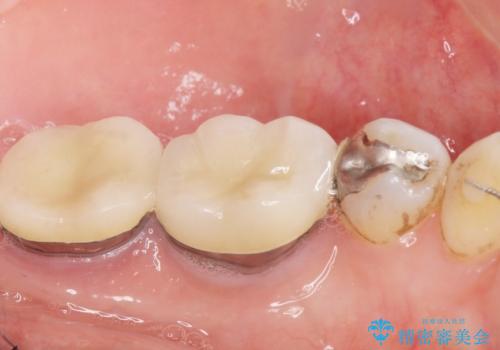

銀歯がなくなったとことで口元の印象が明るくなり、ご満足頂けました。

「これで大きく口を開けて笑っても大丈夫だわ!」と喜んで下さいました。

右上小臼歯(右上5):オールセラミッククラウン エコノミー

下顎両側臼歯(下顎両側67):メタルボンドクラウン エコノミー